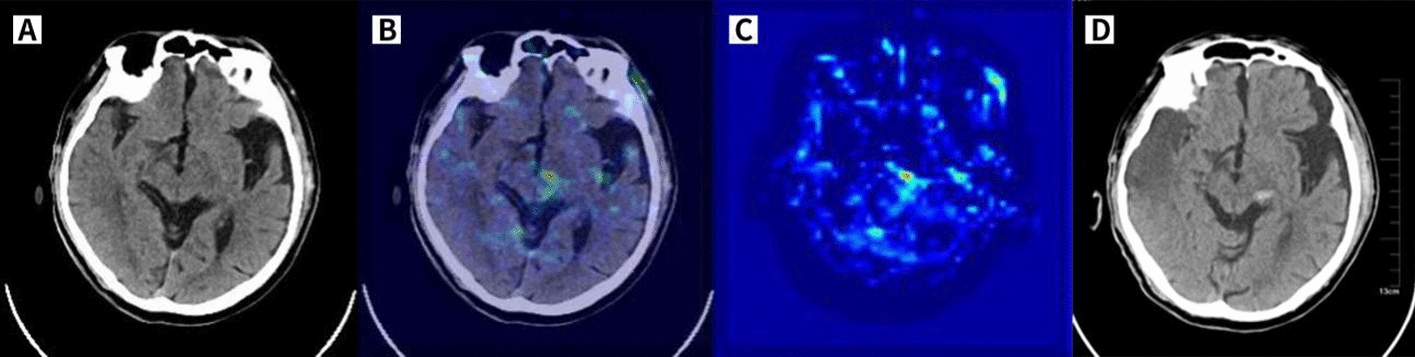

Visualization of the regions on which the WSDL model focussed using gradient-weighted class activation mapping (Grad-CAM)

The activation of the WSDL model when predicting HT was mainly focussed on the brain tissue region related to infarct lesions, small-vessel ischaemia, leukoaraiosis, and atrophy or the location where HT would occur in most cases. Figure 4 shows a typical HT case to visualize the class activation maps (CAMs).

Fig. 4.

CAM of a correctly predicted HT case, as shown in C. The patient was admitted to our hospital with sudden inactivity of the left limb for 2 h, and haemorrhage and clear infarct lesions were not found on baseline NCCT (A). Then, the patient was given rt-PA 56 mg. The cranial NCCT was re-examined within 24 h, and there were HTs in the left thalamus and midbrain cerebral peduncle (D). Superimposing the heatmap on the native image (B) highlights the left thalamus and midbrain cerebral peduncle, which were the regions of HT that occurred after IVT (as shown by the arrow), thus proving that the model predicting upcoming HT was favourable